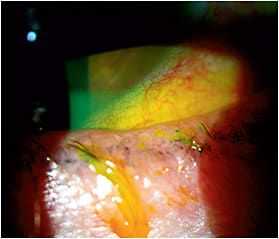

Note the “scalloped” lid margin from gland loss and gland atrophy. You can also see mild saponification, or a foamy tear film. There is also lid telangiectasia, lash loss, misdirected lashes and conjunctival hyperemia.